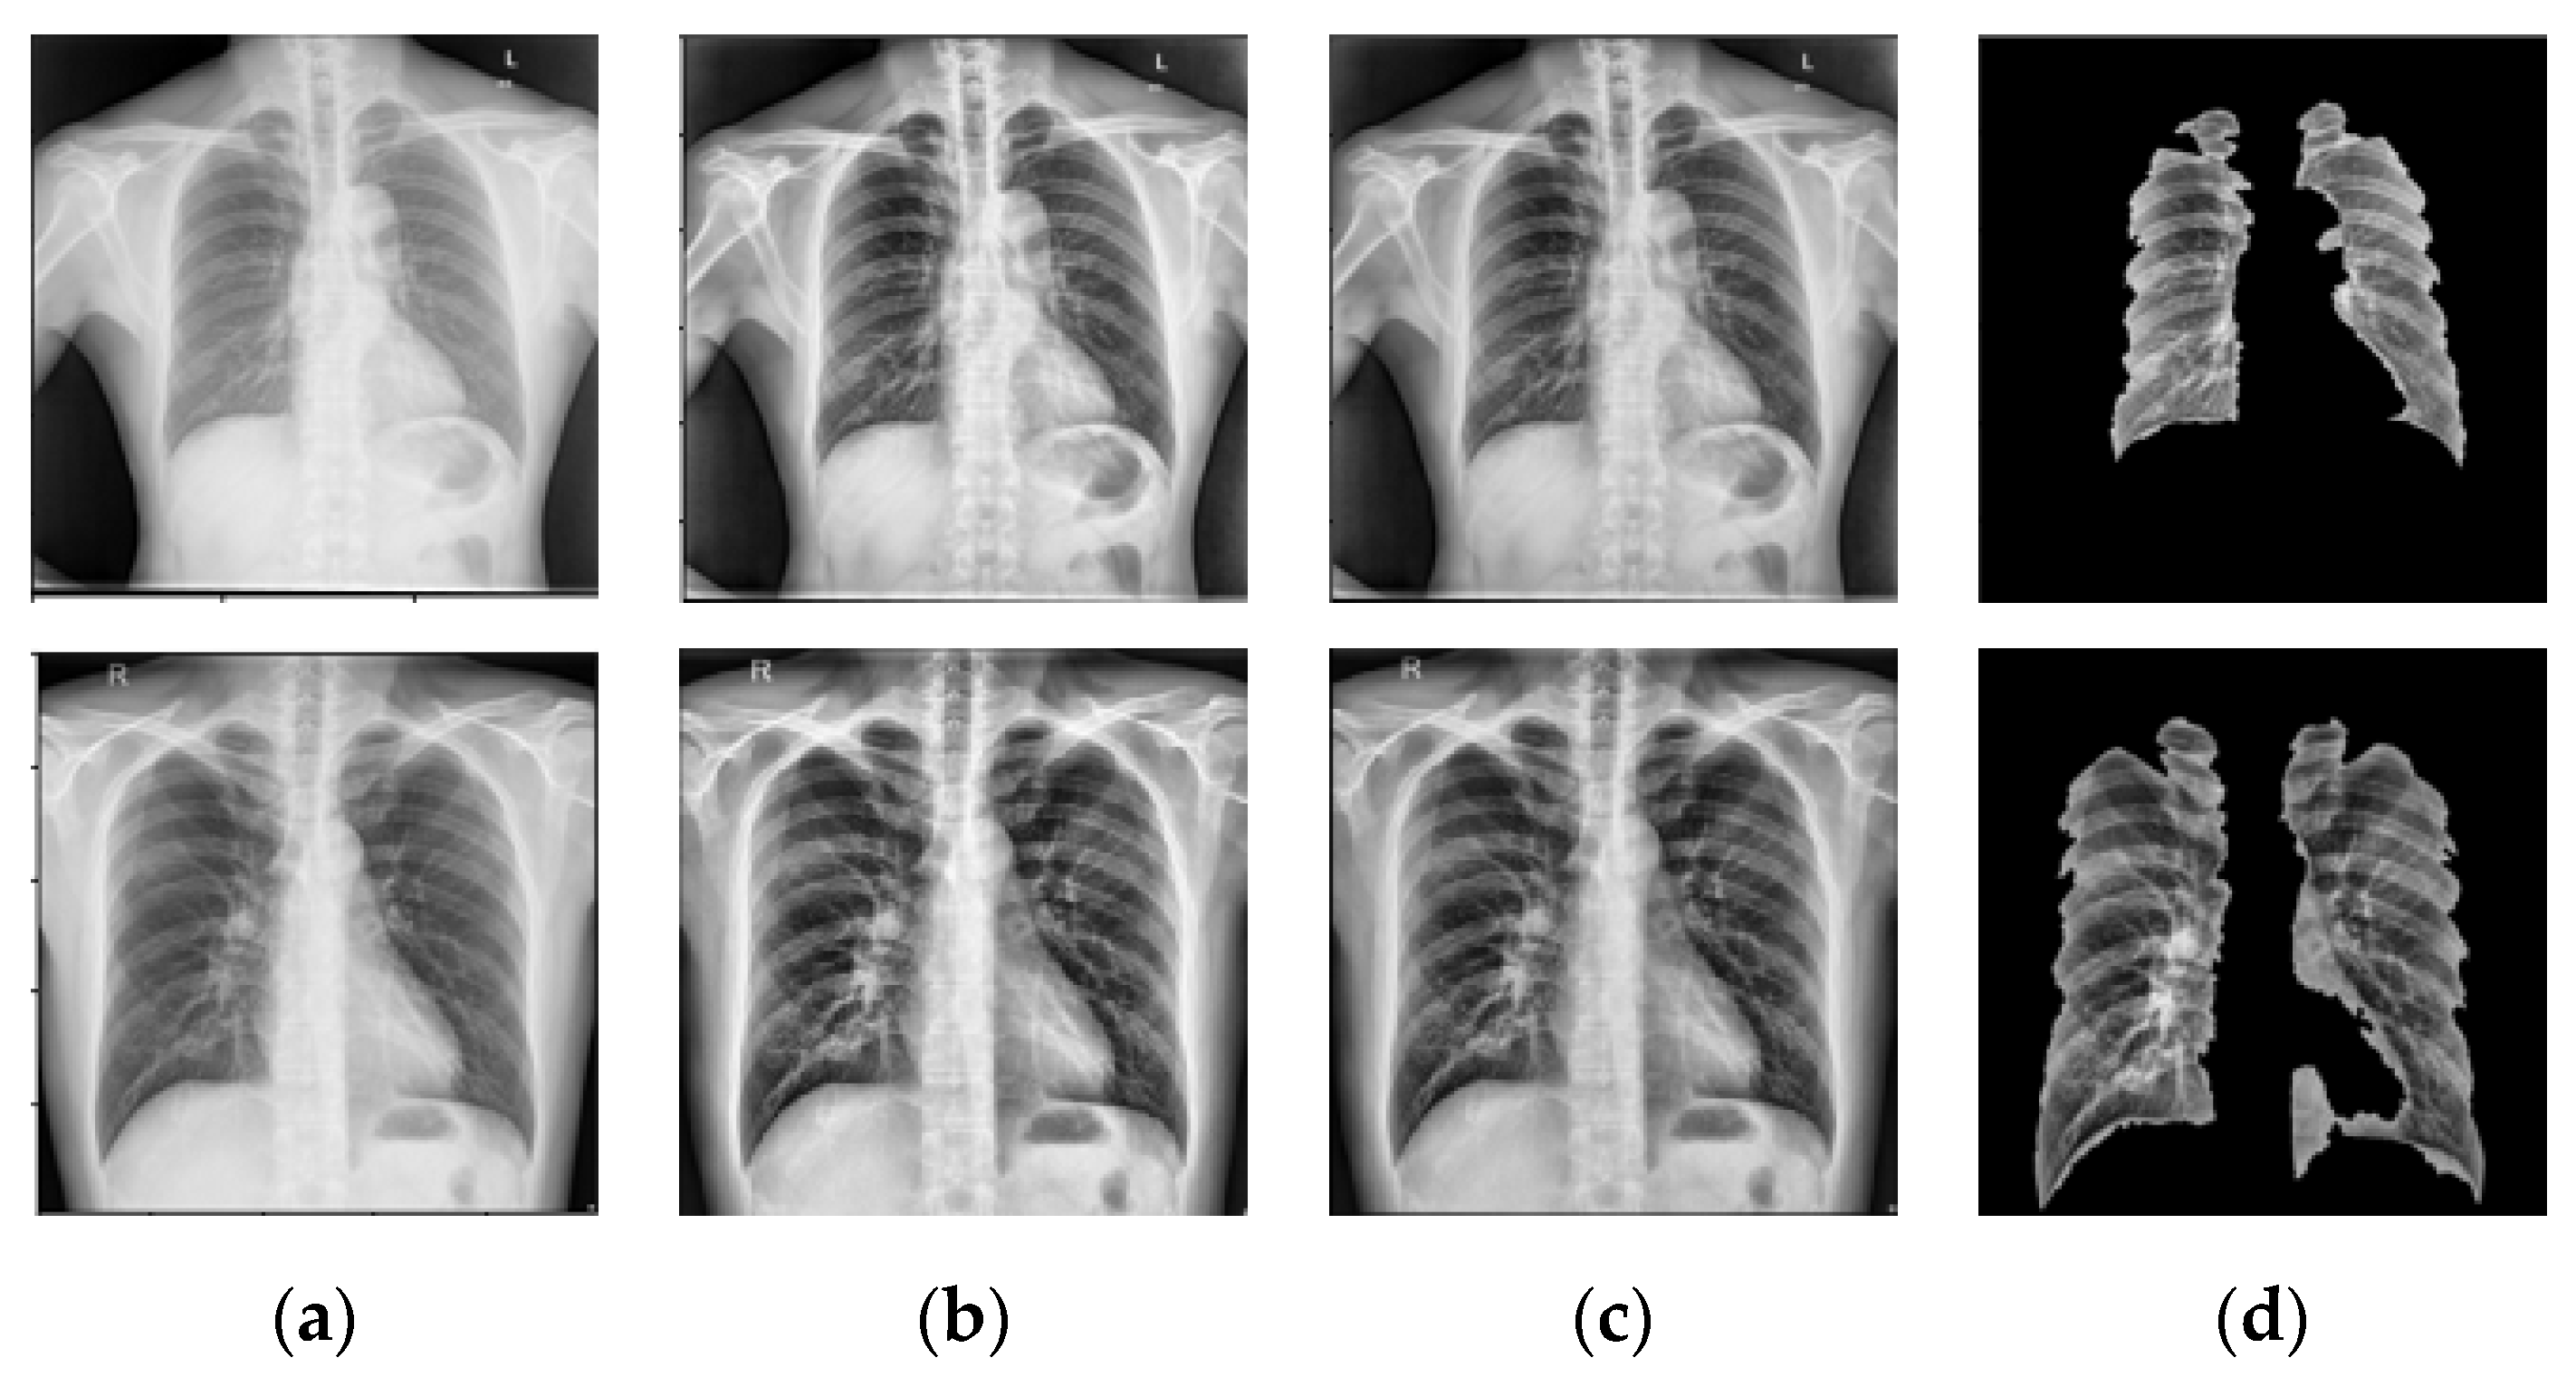

- NLM (National Library of Medicine) dataset [16,20,21]: This was made by two publicly accessible datasets including the Montgomery County CXR set (MC) and Shenzhen (CHN) dataset. The MC dataset was compiled in collaboration with Montgomery County, Maryland, the United States’ Department of Health and Human Services. The collection includes 138 frontal CXRs from Montgomery County’s tuberculosis screening program, where 80 CXRs were normal cases while 58 CXRs had TB manifestations. The X-rays were taken with a Eureka stationary X-ray machine (CR) and provided as 12-bit gray level images in portable network graphics (PNG) format. Moreover, the Digital Imaging and Communications in Medicine (DICOM) format is also available upon request. The X-rays were either 4020 × 4892 or 4892 × 4020 pixels in size. The Shenzhen dataset was collected in collaboration with Shenzhen No. 3 People’s Hospital, Guangdong Medical College, Shenzhen, China. The CXRs were from outpatient clinics and captured as part of the daily hospital routine within a 1-month period, mostly in September 2012, using a Philips DR Digital Diagnost system. The dataset contained 662 frontal CXRs, of which 326 belonged to normal cases while 336 had TB manifestations including pediatric X-rays (AP). The X-rays are provided in PNG format, and can vary in size, but is approximately 3 K × 3 K pixels.

- Belarus dataset [20]: The National Institute of Allergy and Infectious Diseases, Ministry of Health, Republic of Belarus, collected the Belarus Set for a drug resistance study. There are 306 CXRs in the dataset, representing 169 patients. The Kodak Point-of-Care 260 system was used to take chest radiographs with a resolution of 2248 × 2248 pixels. All images in this database had been infected with tuberculosis.

- RSNA dataset [20]: The RSNA pneumonia detection challenge dataset contains approximately 30,000 chest X-ray images, 10,000 of which were normal and the rest were abnormal as well as the lung opacity images. The DICOM format was used for all images. A total of 3094 normal images were taken from this database and the remaining 406 normal images were taken from the NLM database to create a normal database of 3500 chest X-ray images for this study.